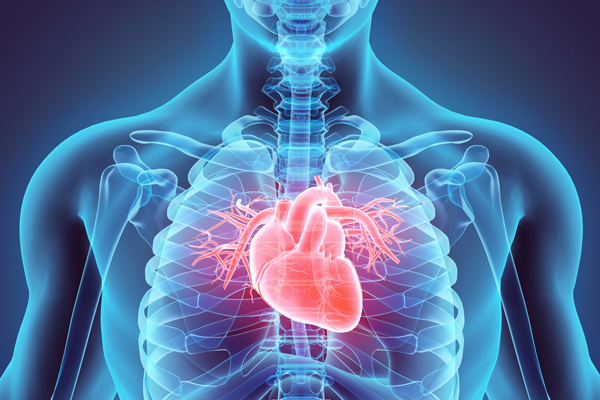

Tim mạch

- Khám và điều trị các bệnh nội khoa, ngoại khoa, sản phụ khoa, nhi khoa,…

- Khám và điều trị các bệnh chuyên khoa như: tim mạch, gan mật, tiêu hóa, hô hấp,…